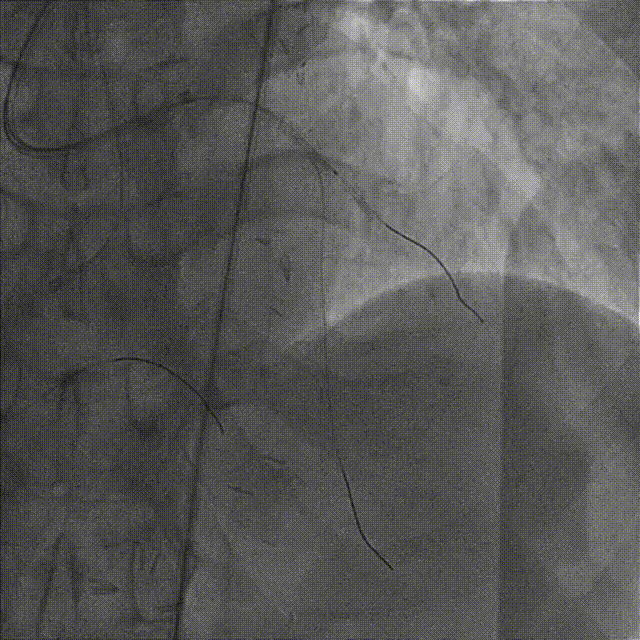

造影示支架定位良好,D1开口受压90%狭窄,交换一根SION导丝穿支架网眼至D1远段,用Pinoeer1.5mm x 15mm、Pinoeer 2.0mm x 15mm球囊至D1开口处扩张。

FOXTROT NC 2.5mm x 15mm、FOXTROT 3.0 mm x 15mm后扩球囊后扩球囊至支架内后扩,以实现支架的充分贴壁,并对LAD远段进行球囊扩张,造影显示TIMI血流III级。

术后行IVUS检查示:支架定位贴壁扩张良好,LAD开口MSA:7.43mm2。